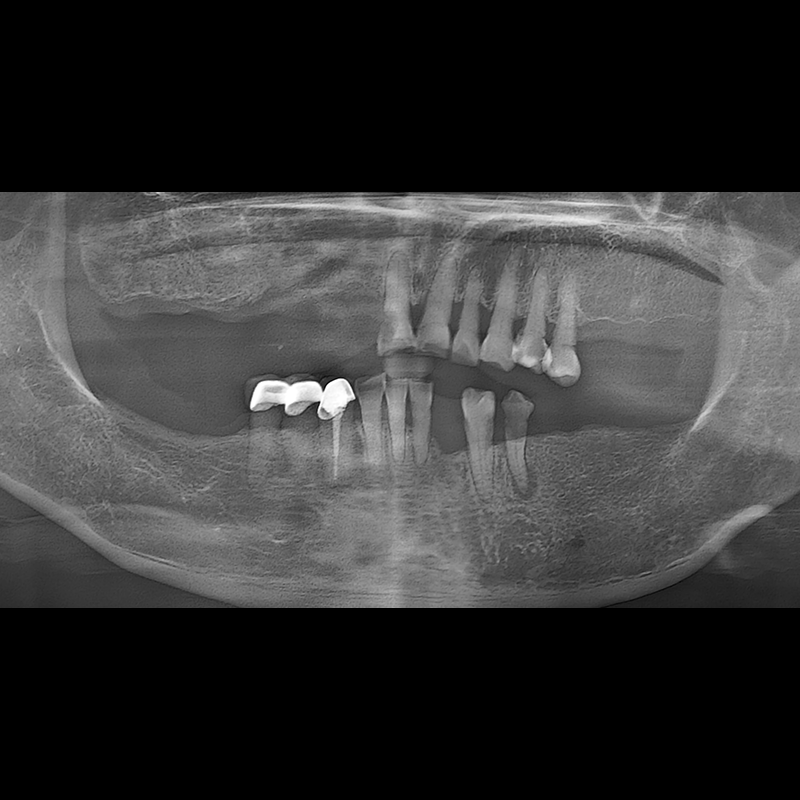

BEFORE AFTER

种植牙前后的照片 2025.05.30

在缺失的牙齿部分和难以挽救的牙齿位置植入了种植牙。